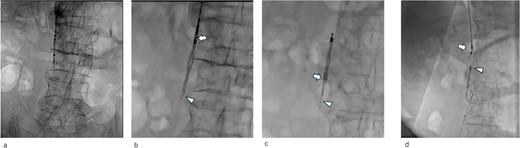

An IVCF was inserted into the inferior vena cava (IVC) using the right internal jugular venous approach. After performing IVC venography (Fig. 2a) using a driver sheath, the IVCF was attempted to deployed. However, the IVCF did not open (Fig. 2b). To retrieve the unopened filter, a plunger was pulled; however, the IVCF and plunger detached (Fig. 2c). We attempted to remove the IVCF via a right femoral venous approach using a snare. However, the snare did not pass through the IVCF because the tip of the leg was attached to the IVC wall or gonadal vein ostium. The hemodynamics of the patient worsened during the procedure. Therefore, we decided to quit additional endovascular retrieval and place a new IVCF. A new IVCF was placed to hold the unopened IVCF at the proximal (head) portion of the unopened IVCF through a right jugular approach (Fig. 2d). An unopened IVCF was placed with pulling the delivery sheath (Fig. 3).

Intraoperative radiographic fluorescence imaging. (a) Pre-deployment venogram of the inferior vena cava (IVC) demonstrating appropriate positioning of the delivery sheath within the IVC prior to inferior vena cava filter (IVCF) placement. (b) The IVCF is not open, and the legs of the IVCF are folded. The IVCF is hung on a plunger. The arrow indicates the tip of the sheath. The arrowheads indicate the folded IVCF legs. (c) The IVCF could not be retrieved because it is detached from the plunger. The arrow indicates the tip of the sheath. The arrowheads indicate the folded IVCF legs. (d) The new IVCF is deployed proximal to the old IVCF.